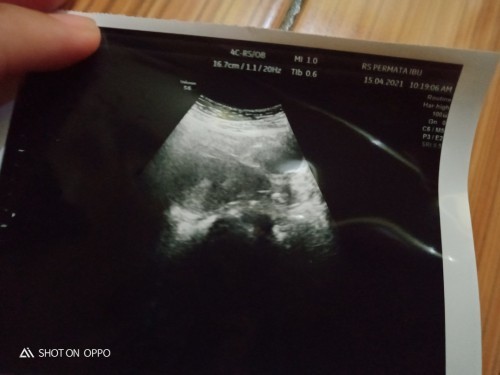

ini saya usia 7w Bun Alhamdulillah sudah terlihat saran USG transvaginal Bun biar lebih jelas karena kalau USG perut usia kandungan segitu memang belum keliatan

USG transvaginal bun. aq juga waktu usg biasa ngga keliatan, pas usg transvaginal janin'a udah keliatan...

7 minggu mah masih kantong bun nanti 10 minggu udh ada janin sama detak jantungnya

waktu aku sih bun USG 5mgg baru keliatan kantung janin nya